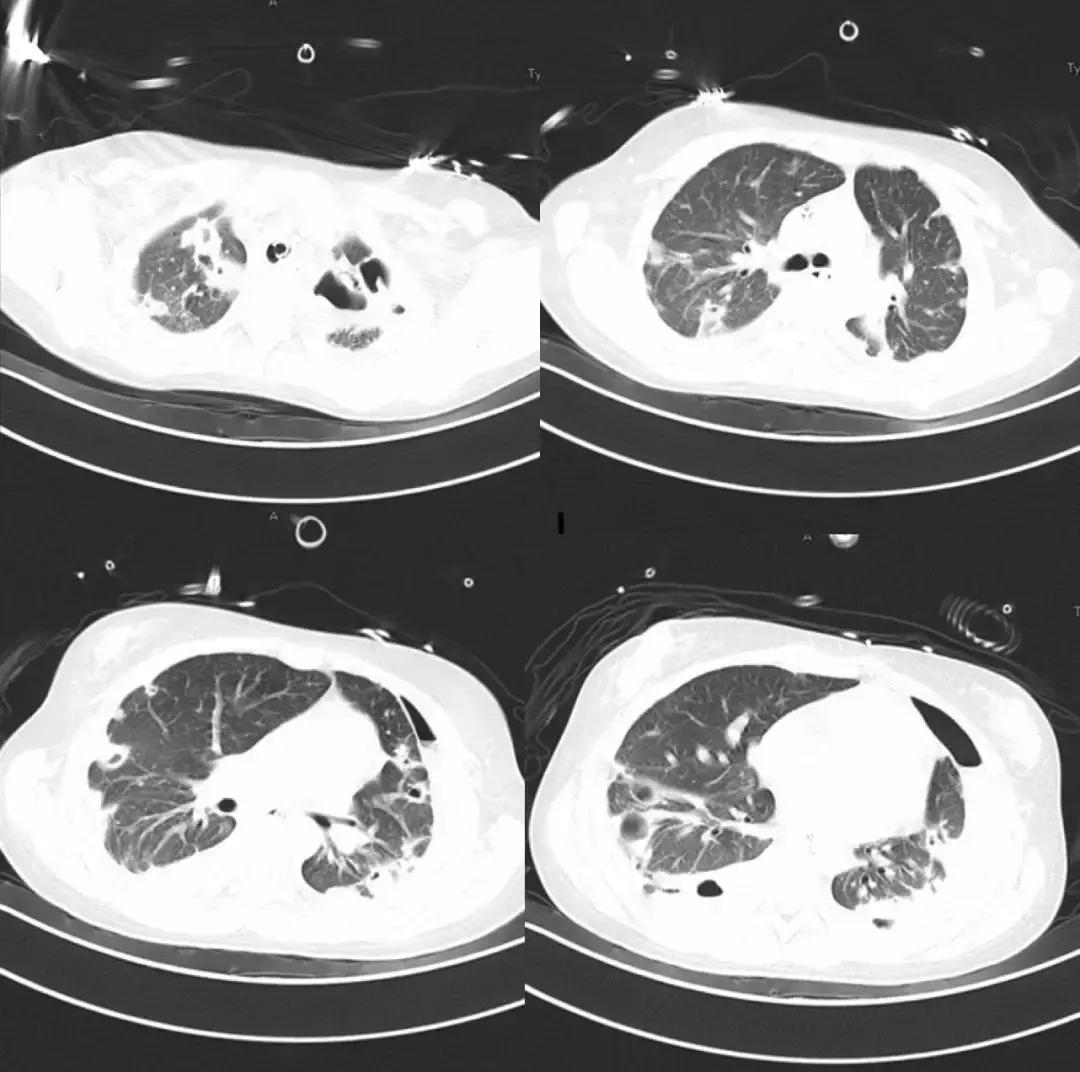

*影像学仍持续变化:

左侧胸腔病变为肺大泡?气胸?如何处理?药物是否需要调整?

*局部气胸引流

- 行左侧胸腔穿刺共两次,共抽出气体约2000ml;

- 患者呼吸困难缓解;

- 患者体温高峰逐渐下移;

- 复查血常规:白细胞9.79*10^9/L;降钙素原0.18ng/ml;血培养阴性